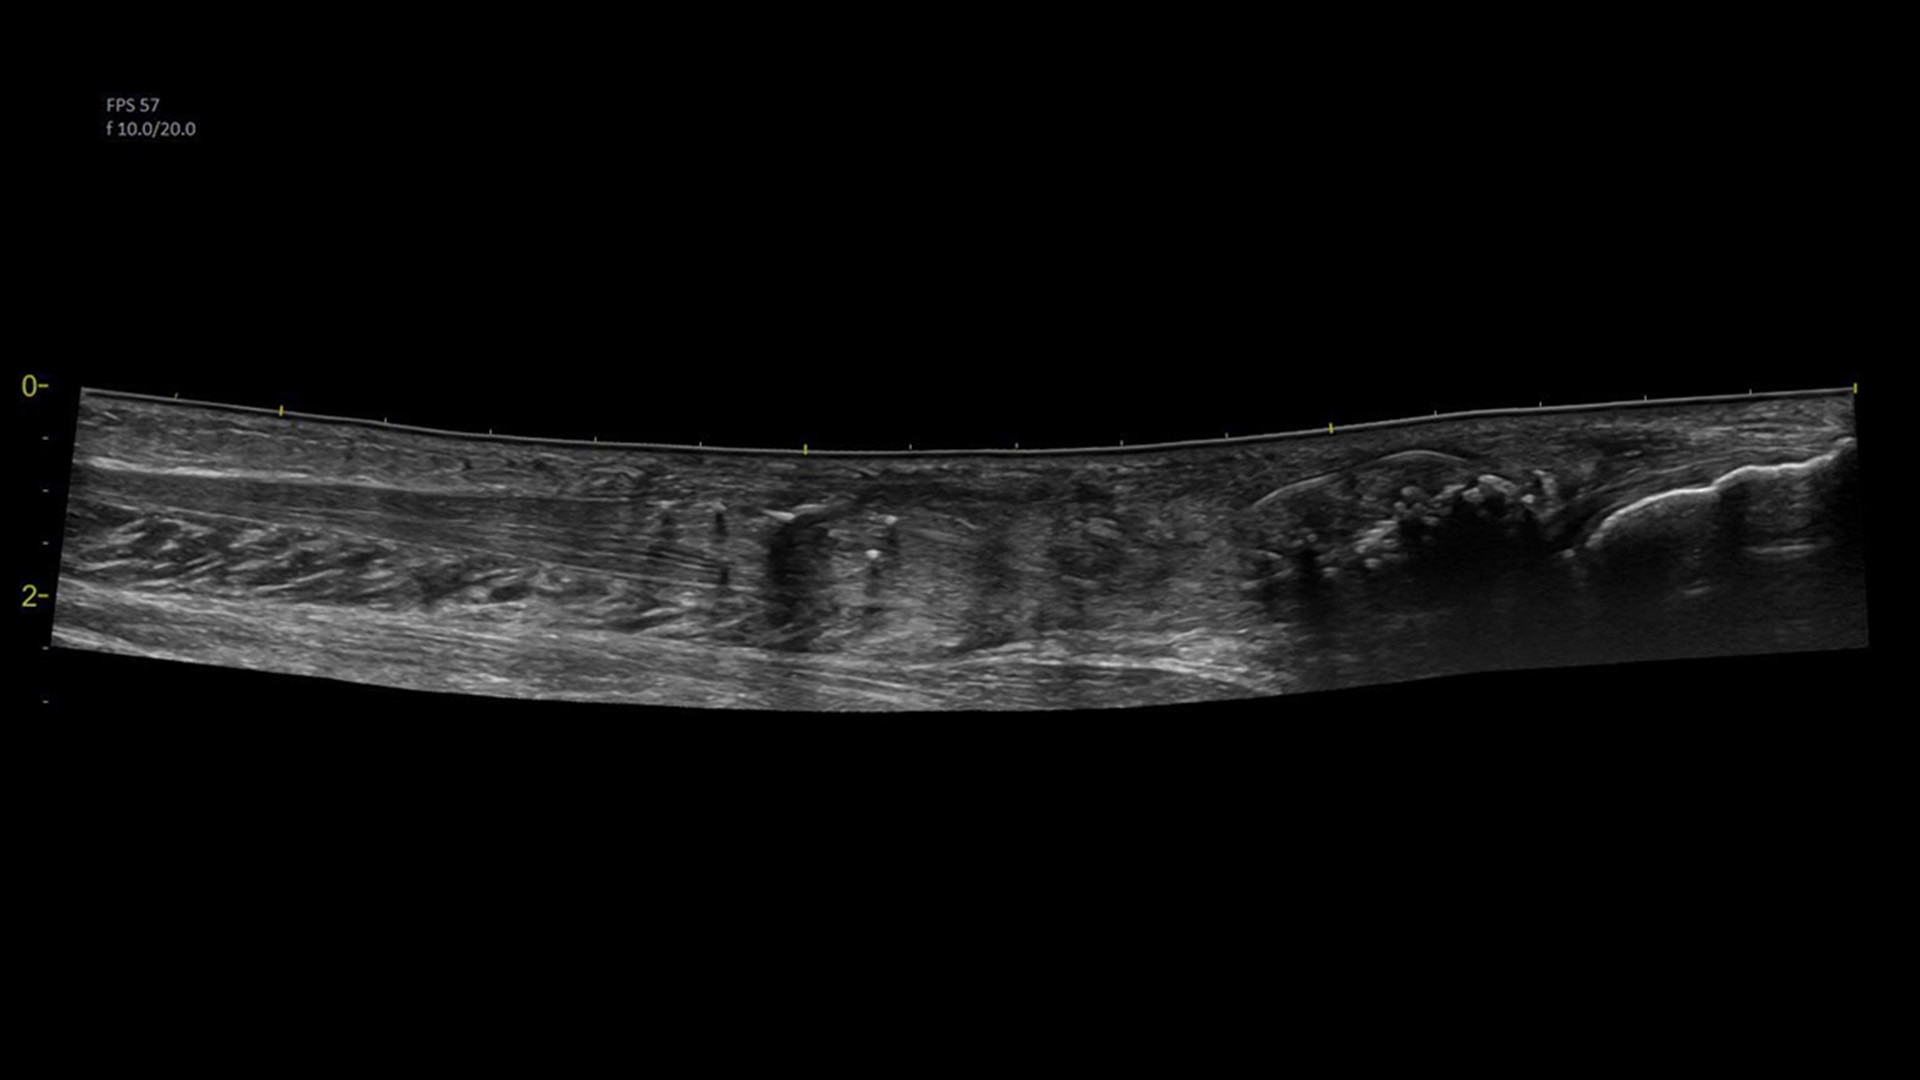

Visualize more anatomy in a single scan with Virtual Convex

This tool provides a wide field of view so users can visualize more large anatomy structures in a single scan.

musculoskeletal-virtual-convex-ci-en

Easily see the anatomy you need to see with Venue View

Supporting diagnostic confidence by constructing a panoramic image from individual frames, Venue View allows you to view up to 60cm of anatomy being scanned with anatomical relationships in one view.1

musculoskeletal-venue-view-ci-en